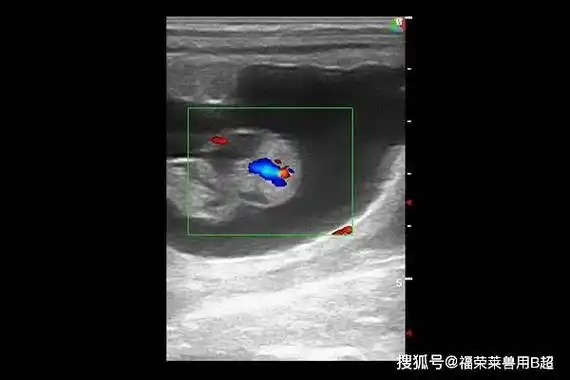

若妇女子宫内膜均匀增厚,极有可能出现内膜增生.

3,子宫腺肌病或子宫肌瘤:内膜受压,导致jz异常增厚,形态曲折,回声不